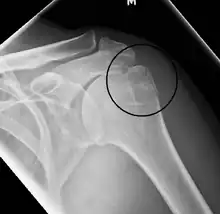

Proximal

Proximal humerus fractures most often occur among elderly people with osteoporosis who fall on an outstretched arm.[9] Less frequently, proximal fractures occur from motor vehicle accidents, gunshots, and violent muscle contractions from an electric shock or seizure.[10][5] Other risk factors for proximal fractures include having a low bone mineral density, having impaired vision and balance, and tobacco smoking.[11] A stress fracture of the proximal and shaft regions can occur after an excessive amount of throwing, such as pitching in baseball.[6]

Definitive diagnosis of humerus fractures is typically made through radiographic imaging. For proximal fractures, X-rays can be taken from a scapular anteroposterior (AP) view, which takes an image of the front of the shoulder region from an angle, a scapular Y view, which takes an image of the back of the shoulder region from an angle, and an axillar lateral view, which has the patient lie on his or her back, lift the bottom half of the arm up to the side, and have an image taken of the axilla region underneath the shoulder.[9] Fractures of the humerus shaft are usually correctly identified with radiographic images taken from the AP and lateral viewpoints.[12] Damage to the radial nerve from a shaft fracture can be identified by an inability to bend the hand backwards or by decreased sensation in the back of the hand.[5] Images of the distal region are often of poor quality due to the patient being unable to extend the elbow because of pain. If a severe distal fracture is suspected, then a computed tomography (CT) scan can provide greater detail of the fracture. Nondisplaced distal fractures may not be directly visible; they may only be visible due to fat being displaced because of internal bleeding in the elbow.[7]

Fractures of the humerus are classified based on the location of the fracture and then by the type of fracture. There are three locations that humerus fractures occur: at the proximal location, which is the top of the humerus near the shoulder, in the middle, which is at the shaft of the humerus, and the distal location, which is the bottom of the humerus near the elbow.[9] Proximal fractures are classified into one of four types of fractures based on the displacement of the greater tubercle, the lesser tubercle, the surgical neck, and the anatomical neck, which are the four parts of the proximal humerus, with fracture displacement being defined as at least one centimeter of separation or an angulation greater than 45 degrees. One-part fractures involve no displacement of any parts of the humerus, two-part fractures have one part displaced relative to the other three; three-part fractures have two displaced fragments, and four-part fractures have all fragments displaced from each other.[13][14][3] Fractures of the humerus shaft are subdivided into transverse fractures, spiral fractures, "butterfly" fractures, which are a combination of transverse and spiral fractures, and pathological fractures, which are fractures caused by medical conditions.[12] Distal fractures are split between supracondylar fractures, which are transverse fractures above the two condyles at the bottom of the humerus, and intercondylar fractures, which involve a T- or Y-shaped fracture that splits the condyles.[7]